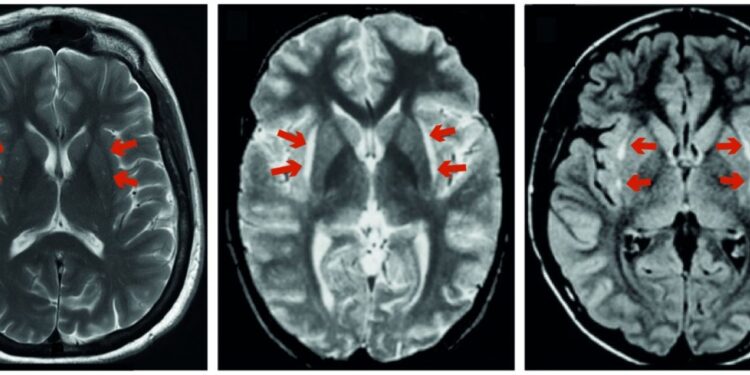

Um novo artigo de revisão, publicado na revista Brain , mostrou que uma região mal compreendida do cérebro chamada claustrum pode desempenhar um papel importante na forma como experimentamos a dor. Uma colaboração de grupos de pesquisa da Universidade de Oxford do Departamento de Fisiologia, Anatomia e Genética (DPAG), o Departamento Nuffield de Neurociências Clínicas (NDCN) e Psicologia Experimental (EP) descobriu novas pistas sobre a função de um dos mais densamente interconectados, ainda que raramente estudadas, áreas do cérebro.

Eles também descobriram uma ligação subestimada entre o claustro e a dor. Já se sabe que existem ligações entre o claustro e a percepção, a saliência e o ciclo sono-vigília, mas esta é a primeira vez que uma equipe de pesquisa mostra como o claustro pode estar mais envolvido na experiência debilitante da dor.

Os pesquisadores encontraram vários casos registrados de infecção, autoimune ou outro processo que atacou o claustro em particular e, analisando os resultados desses estudos e outros, os sintomas mais comuns nos pacientes foram comprometimento cognitivo e convulsões.